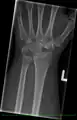

Left hand x-ray with Kienbock's Disease showing 4 mm negative ulnar variance and Kienbock's Disease Stage IIIB

Left hand x-ray with Kienbock's Disease